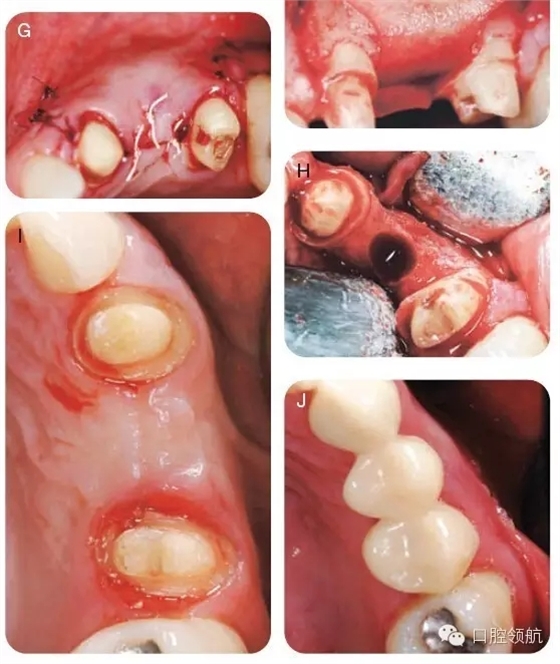

用2%利多卡因(1/100000腎上腺素)行下牙槽后、中神經(jīng),腭大神經(jīng)阻滯麻醉,局部浸潤麻醉。附加兩個(gè)垂直方向的松弛切口使得視野更加清晰并減低術(shù)后瓣撕裂的可能,上頜右側(cè)1/4區(qū)域翻開全厚瓣以充分暴露骨皮質(zhì)(圖6A~C)。暴露術(shù)區(qū),用圓形金剛鉆去除該區(qū)的骨皮質(zhì),使得術(shù)區(qū)有血液流出。打入兩個(gè)10mm的支帳螺絲并且確認(rèn)其穩(wěn)定(圖6D)。取稍過量的脫礦凍干骨置于該區(qū)域(圖6E)。放置堅(jiān)固的可吸收膠原膜( O s s e o g u a r d -Collagen Matrix, Inc, Franklin Lakes,NJ, USA)于移植物上(圖6F),復(fù)位瓣并原位縫合。組織愈合良好(圖6G)。在GBR術(shù)后6個(gè)月,再次麻醉并暴露術(shù)區(qū),制備直徑為4.1mm的植入位點(diǎn),使得頰舌側(cè)有足夠的余留骨,以確保組織的長期穩(wěn)定性并防止組織退縮(圖6H),在最終固定冠修復(fù)前,拍攝照片,顯示牙槽骨寬度顯著改善(圖6I,J),圖7為最終修復(fù)當(dāng)日照片。

圖6 (A~J)手術(shù)時(shí)的口內(nèi)照。